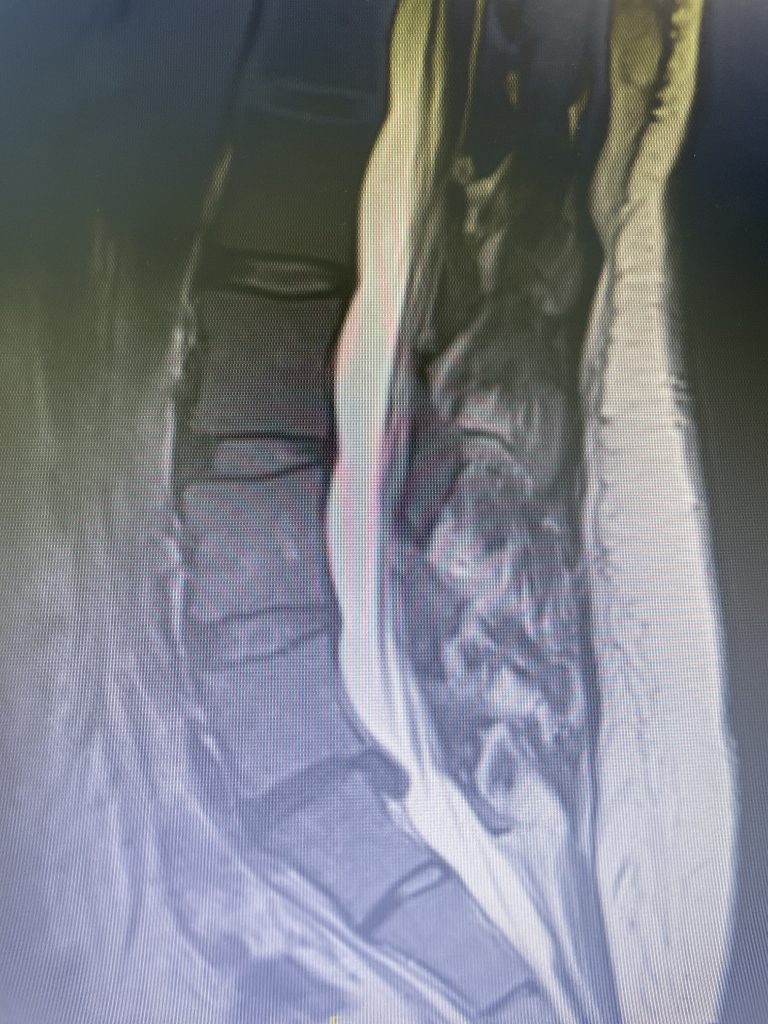

A 35-year-old female presents with severe low back pain and progressive left leg pain. She had initially presented nine months prior with mainly low back pain with mild left leg symptoms. She had an MRI (Fig 1) demonstrating a transitional L5 lumbar vertebra. This L5 vertebra is sacralized in that it is more anatomically associated with the sacral level with a rudimentary disc between it and the segment below. Because of the rudimentary disc there is very little movement at that level, hence more stress is put on the segment above.

Figure 1